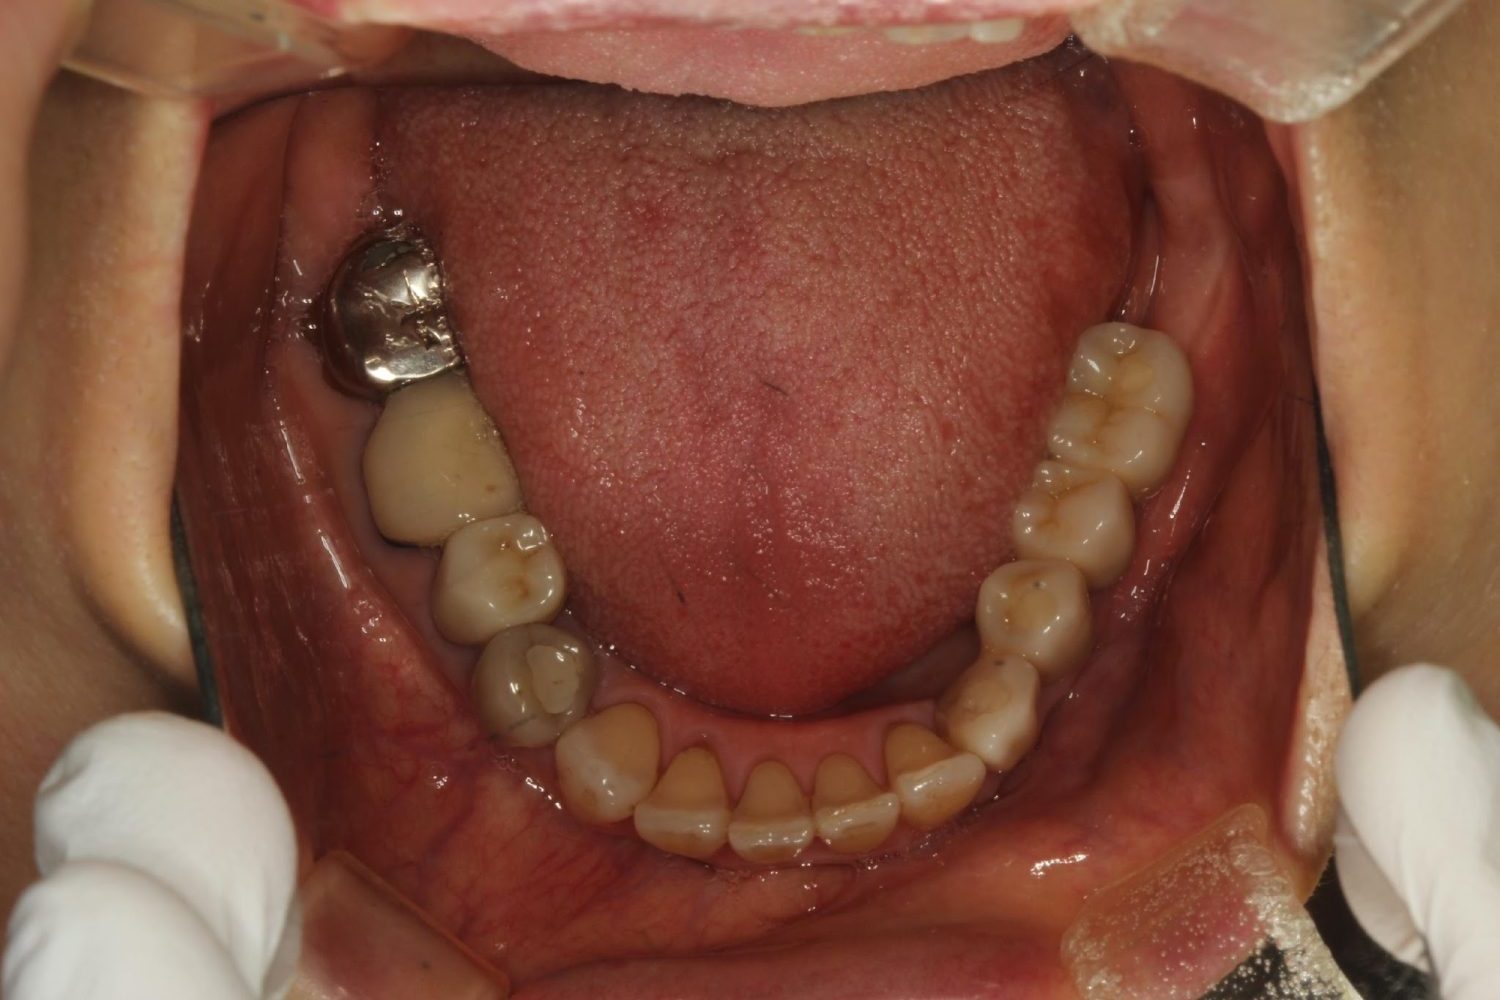

インプラント治療の症例紹介④

Before

After

主訴

義歯による疼痛

治療内容

下顎舌側に骨隆起があり義歯困難な状態。保存不可能な歯の抜歯を行い、インプラントを埋入し咬合再構成を行った。

治療費

2,851,200円(税込)

治療期間

29ヶ月

通院回数

26回

想定されたリスク

※咬合力の強い方なので、予防的にマウスピースの装着が必要。インプラント周囲炎の恐れがありました。

歯の欠損の対合歯の挺出等を修正し咬合平面を揃え咬合再構成を行った症例。